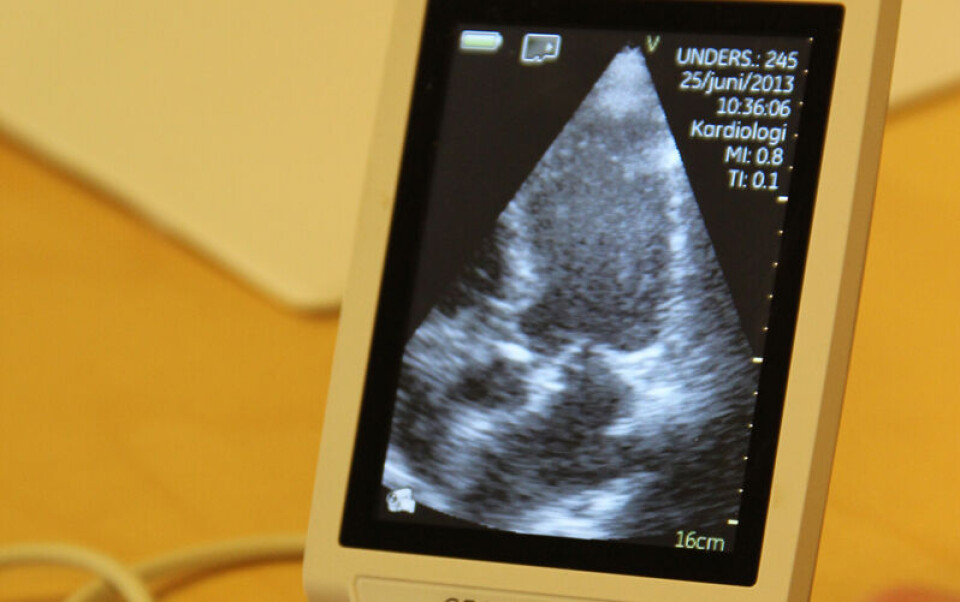

Ultralydbildene kommer opp på skjermen til den bærbare PC-en på pulten.

Bildene er grumsete og utydelige, og endrer seg etter hvert som skanneren beveger seg. Men på skjermen dukker det i tillegg opp felter med farger og ord.

På et rødt felt i bildet står det «blood». Feltet viser at her går det en blodåre i armen. På samme måte er bein markert med oransje og ordet «bone».